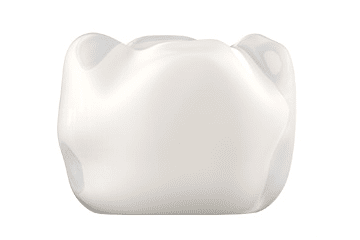

레진 치아색과 유사하며 충치부위가 크고

눈에 띄는 곳에 사용하는 것이 적합합니다. -

세라믹 도자기 소재로 치아의 색과

유사하며 강도가 좋습니다. -

지르코니아 생체친화적 소재로 강도가 우수하여

힘이 강한 어금니에도 사용할 수 있으며,

심미성 또한 뛰어납니다.